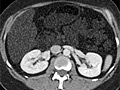

Computed Tomography (CT) Scan of the BodySkip to the navigationTest OverviewA computed tomography (CT) scan uses

X-rays to make detailed pictures of structures inside

of the body. During the test, you will lie on a table that is

attached to the CT scanner, which is a large doughnut-shaped machine. The CT

scanner sends X-rays through the body area being studied. Each rotation of the

scanner provides a picture of a thin slice of the

organ or area. All of the pictures are saved as a

group on a computer. They also can be printed. In some cases, a

pictures. A CT scan can be used to study all parts of your

body, such as the chest, belly, pelvis, or an arm or leg. It can take pictures

of body organs, such as the liver,

pancreas,

intestines,

kidneys,

bladder,

adrenal glands, lungs, and heart. It also can study

blood vessels, bones, and the spinal cord. Fluoroscopy CT